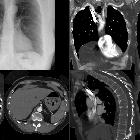

Ausgedehnter

kongenitaler Zwerchfelldefekt links. Magenluft und Spitze der Magensonde im Sinne einer Hernie oberhalb des Zwerchfellniveaus. Herz und Thymus nach rechts verlagert (Mediastinalshift). Trachealtubus nach rechts abweichend.

Thoraxmagen

mit erheblicher Luftfüllung. Nebenbefundlich erhebliche Höhenminderung mittlerer BWK mit Hyperkyphose.